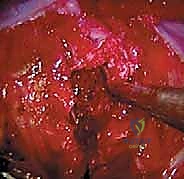

الخطوة الثالثة: الدخول إلى تجويف الصدر وإفراغ الرئة

يتم إدخال الكاميرا، وتظهر الصورة بدقة 4K على الشاشات الكبيرة في غرفة العمليات. يتم إفراغ الرئة بالكامل (Lung deflation)، مما يكشف عن التشريح الداخلي للصدر: العمود الفقري، الأضلاع، الشريان الأورطي (أو الوريد الأجوف حسب الجانب)، والسلسلة العصبية الودية.